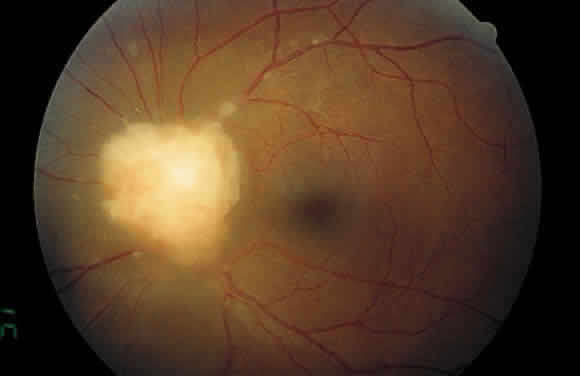

Examination of the posterior segment of the eye must also include an examination of the optic nerve head. Disc edema or hyperemia is frequent in uveitis patients, often preceding the development of macular edema. Neovascularization of the disc is another abnormality that may develop in patients with severe uveitis.36 The optic nerve head may also be a site of granuloma formation (Fig. 12).

|